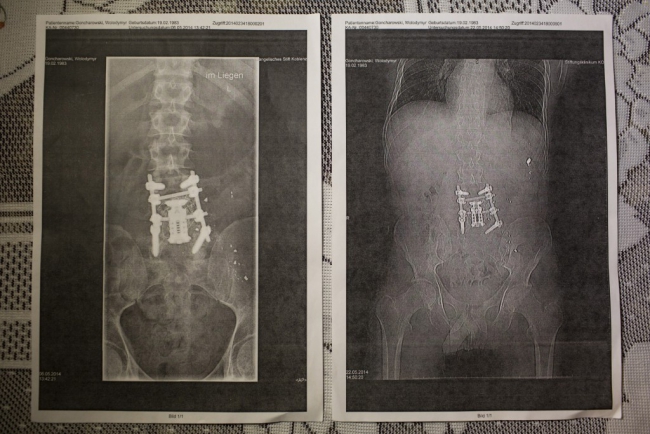

Владимир Гончаровский

Ему 31 год, женат, отец четырех детей, был тяжело ранен 20 февраля 2014 выстрелами - дважды в спину и в правую руку. Он спасал раненых участников Евромайдана, в которых стреляли правоохранители на улице Институтской в Киеве. Ему провели многочисленные операции в Украине и Германии, но его состояние остается чрезвычайно сложным.

У него диагностировали гепатит С. Владимир думает, что мог подхватить вирус при получении медицинской помощи после ранения на Евромайдане.